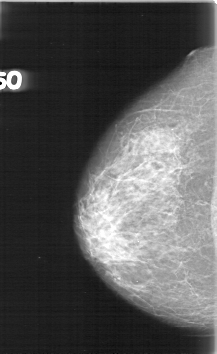

D_4016_1.LEFT_CC

LEFT_CC LINES 5386 PIXELS_PER_LINE 3091 BITS_PER_PIXEL 12 RESOLUTION 43.5 OVERLAY